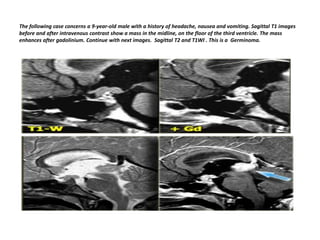

The following case concerns a 9-year-old male with a history of headache, nausea and vomiting. Sagittal T1 images

enhances after gadolinium. Continue with next images. Sagittal T2 and T1WI . This is a Germinoma.